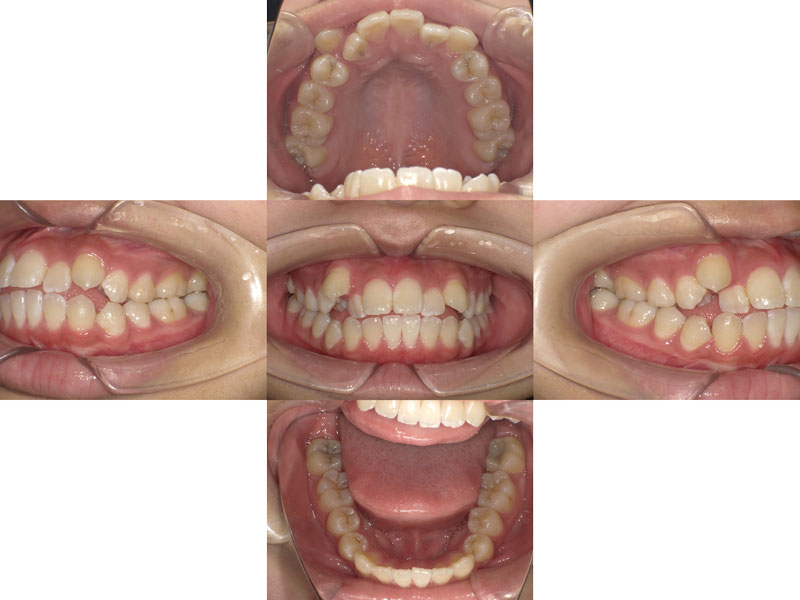

Before

患者様 16歳 女性

※矯正治療開始時

患者様のお悩み(主訴) ・歯並びが悪い(見た目)

・ご飯の時うまく咬めていない気がする(機能的)

・矯正専門医を受診したところ、小臼歯抜歯が必要といわれて悩んでいる

診断 ClassⅠ 叢生 開口 顎変位